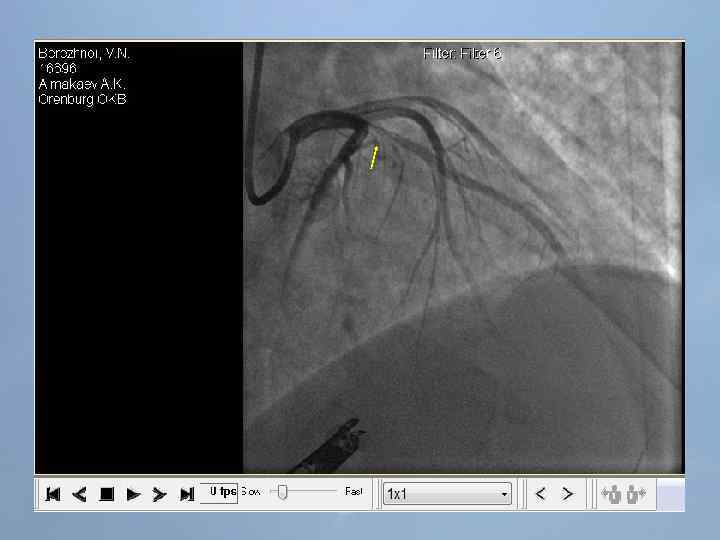

Пациент Б. , 54 года 29. 08. 13 около 10: 00, находясь на рабочем месте, почувствовал боль в груди. После 2 -ух приемов нитроспрея боль не уменьшилась, вызвал СМП. В 10: 20 первой бригадой СМП зафиксирован подъем ST на ЭКГ, начата ТЛТ, вызвана реанимационная бригада. В 10: 50 на месте вызова в присутствии реаниматолога у пациента развивается остановка кровообращения по типу фибрилляции желудочков. Выполнялась СЛР с непрямым массажем сердца, ИВЛ мехом, дефибрилляцией. В течение транспортировки фибрилляция рецидивировала еще 4 раза. Пациент доставлен в ООКБ в 11: 30, минуя приемное отделение госпитализирован в ОРИТ ОИМ.

Проведенные мероприятия: Обезболивание – морфин 1%-1 мл; Введена полная доза пуролазы – 6 млн МЕ; Дана нагрузочная доза клопидогрела - 300 мг; Начата в/в инфузия гепарина – 1000 МЕ/час; Дофамин 4% - в/в через ДЛВ; С противоаритмической целью: Кордарон 300 мг болюсом, затем 600 мг – капельно; Лидокаин 120 мг в/в; Магния сульфат 25% - 15 мл в/в; Калия хлорид 5% - 10 мл в/в.